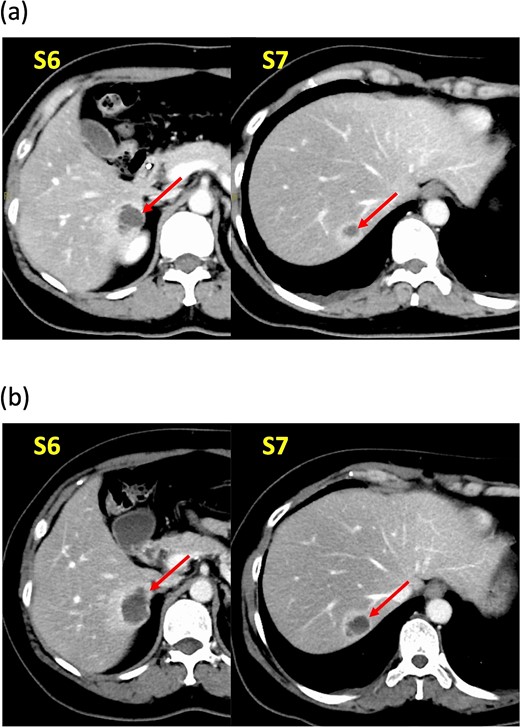

A 52-year-old woman was admitted to our hospital for the evaluation and treatment of multiple cystic liver tumors. Two years earlier, dynamic computed tomography (CT) had detected multiple cystic tumors in segments 6 (S6) and 7 (S7), which were subsequently monitored (Fig. 1a). The patient showed no symptoms; laboratory tests for tumor markers such as α-fetoprotein, protein induced by vitamin K absence or antagonist-II, carcinoembryonic antigen, and carbohydrate antigen 19–9 were within normal ranges. Dynamic CT identified two low-density tumors with peripheral enhancement in the portal phase, featuring cyst-like internal septa (Fig. 1b), which showed slow enlargement over 2 years. Magnetic resonance imaging (MRI) using gadoxetic acid (gadolinium-ethoxybenzyl-diethylenetriamine pentaacetic acid; EOB Primovist®) revealed that tumors appeared as low intensity signals on T1-weighted imaging and high intensity signals on T2-weighted imaging and diffusion-weighted imaging. Additionally, a 7-mm lesion was observed at the S7/8 boundary (Fig. 2a and b). Positron emission tomography-CT (PET-CT) showed abnormal uptake in S6 and S7 tumors but not in the S7/8 lesion (Fig. 3). CT during hepatic arteriography (CTHA) demonstrated well-contrasted tumors at the periphery, with no contrast enhancement in the center (Fig. 4a). Moreover, CTHA detected a new tumor in S8, displaying clear and uniform contrast but not visible with other imaging modalities (Fig. 4b).

Magnetic resonance imaging findings. Known tumors are visible in S6, S7, and an additional tumor is found at the S7/8 boundary. These tumors appeared as low-intensity lesions on (a) T1-weighted images and (b) high-intensity lesions on T2-weighted images.